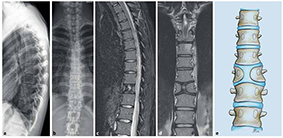

congenitalis scoliosis (veleszületett gerincferdülés)

Az ismert eredetű csoportba (az összes eset kb. 20%-a) azok az esetek tartoznak, ahol a gerincferdülés kialakulásának oka ISMERT (pl. alapbetegség miatt, annak talaján, velejárójaként alakult ki). Ebben a csoportban a leggyakoribb típus az ún. congenitalis scoliosis (veleszületett gerincferdülés), amely a csigolyafejlődési rendellenességre utal. Ezek a rendellenességek, elváltozások bár tipizálhatók, de alapvetően mindig egyéni megjelenést mutatnak, ezért a kezelési terv, a kezelés menete mindig EGYÉNI. Ennél fogva általános szakmai protokoll, kezelési metódus sem létezik, minden páciens egyéni utat jár be.